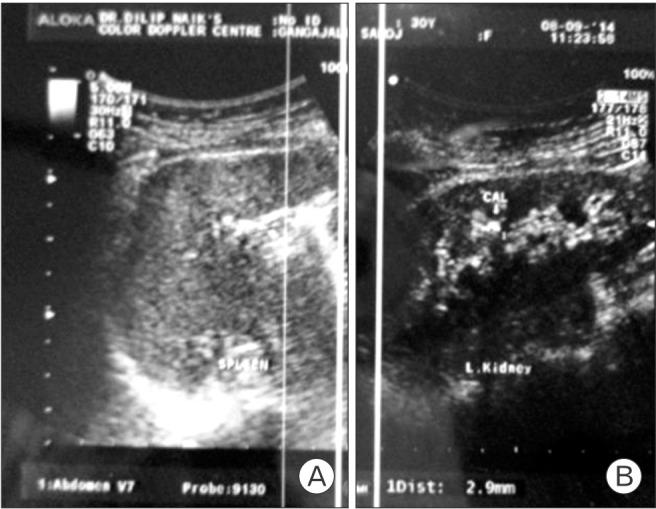

Intrauterine contraceptive devices (IUCDs) are a common form of reversible contraception owing to fewer systemic side effects and low cost, especially in a developing country like India. However, IUCDs are not without complications. Migration of a device into adjacent organs is the most morbid of all the documented complications. A patient who presents with a history that suggests loss or disappearance of an IUCD thread associated with urinary symptoms should raise suspicions that a device may have migrated into the bladder. Physicians should also be aware of possible secondary vesical calculus formation. Further radiological investigations and appropriate management are warranted. We present a case report describing the migration of an IUCD into the bladder with secondary calculus formation.

宫内节育器(IUCDs)是一种常见的可逆避孕方式,因其全身副作用较少且成本低廉,在印度这样的发展中国家尤为常用。然而,IUCDs并非没有并发症。节育器移位至邻近器官是所有已记录并发症中最严重的一种。对于有IUCD尾丝丢失或消失病史且伴有泌尿系统症状的患者,应怀疑节育器可能已移位至膀胱。医生还应意识到可能会继发膀胱结石形成。需要进一步进行影像学检查并采取适当的治疗措施。我们报告一例病例,描述了一枚IUCD移位至膀胱并继发结石形成的情况。